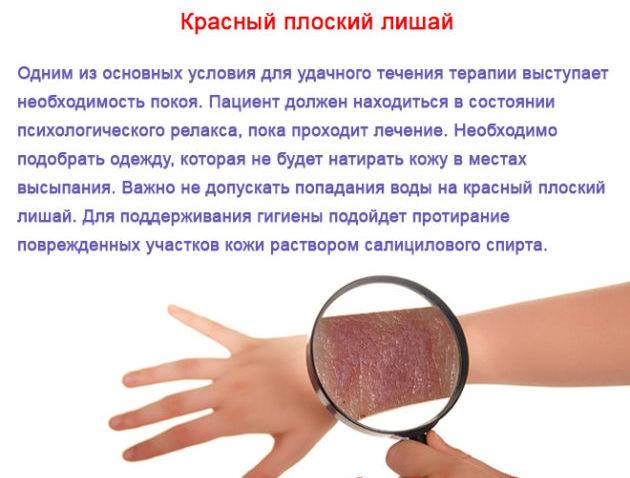

Фото Красного Плоского

Фото Красного Плоского 103 фото